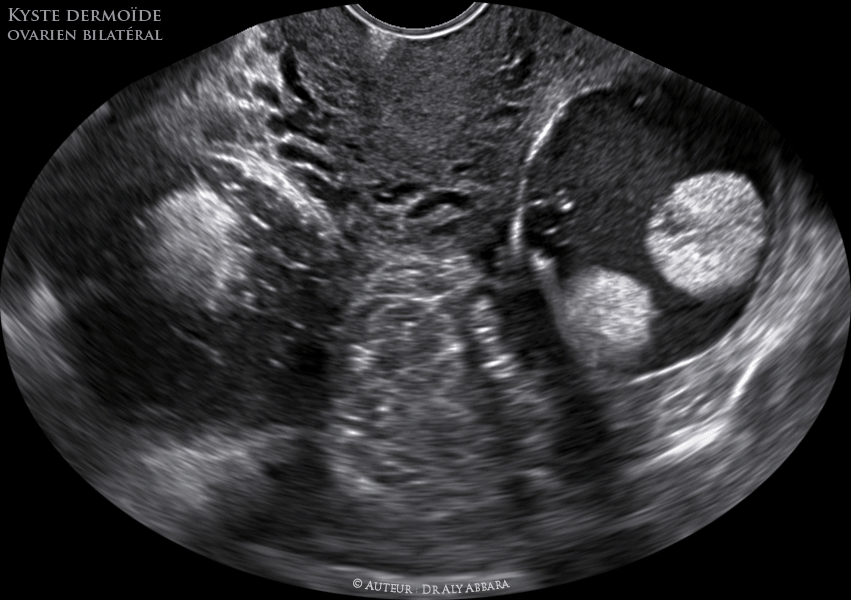

Si la plupart du temps un kyste dermoïde ovarien ne touche qu'un seul ovaire, il peut dans certains cas, être présent sur les deux ovaires en même temps A la différence des autres kystes ovariens, il apparaît à partir de cellules immatures présentes dans l'ovaire et qui proviennent des ovocytesOn peut donc retrouver dans les kystes dermoïdes des tissus comme des petits Kyste ovarien et grossesse ce qu'il faut savoir Les kystes ovariens sont assez courants chez la femme en âge de procréer Dans la majorité des cas, ils ne posent pas de problèmes majeurs, ni pour tomber enceinte, ni durant la grossesse Lorsqu'ils sont plus gênants, un traitement approprié peut être mis en placeLe kyste est le plus souvent bénin "Le fait qu'il apparaisse et disparaisse doit rassurer la femme, affirme la spécialisteMais une boule dans un sein qui ne partirait pas aux prochaines règles doit amener à consulter", conseilletelle Si un nodule persiste dans le temps toujours au même endroit ou s'il apparait après la ménopause

Ovaire Teratome Benin Bilateral Kyste Dermoide Echographie